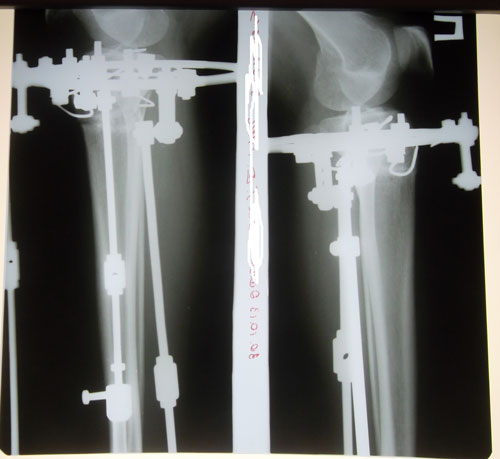

Ножки на сегодня

Ножки в норме, продолжаем фиксацию! Не забывайте про рентгеновский снимок в 2 месяца с момента операции. (с доставкой до адреса клиники). Девочки, это касается ВСЕХ!!!

Дата операции 02.07.2013г.

Дата снятия аппаратов 30.10.2013г.

Срок лечения 118 дней.